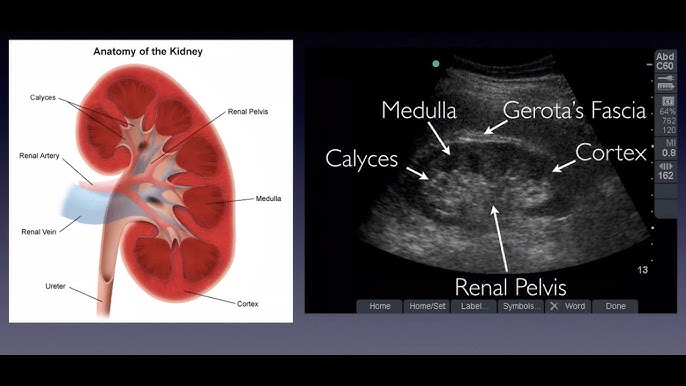

3. kép:

A vese ultrahangos képe

Ezen a képen a vese sematikus ábrája és mellette az ultrahangos képe látható.